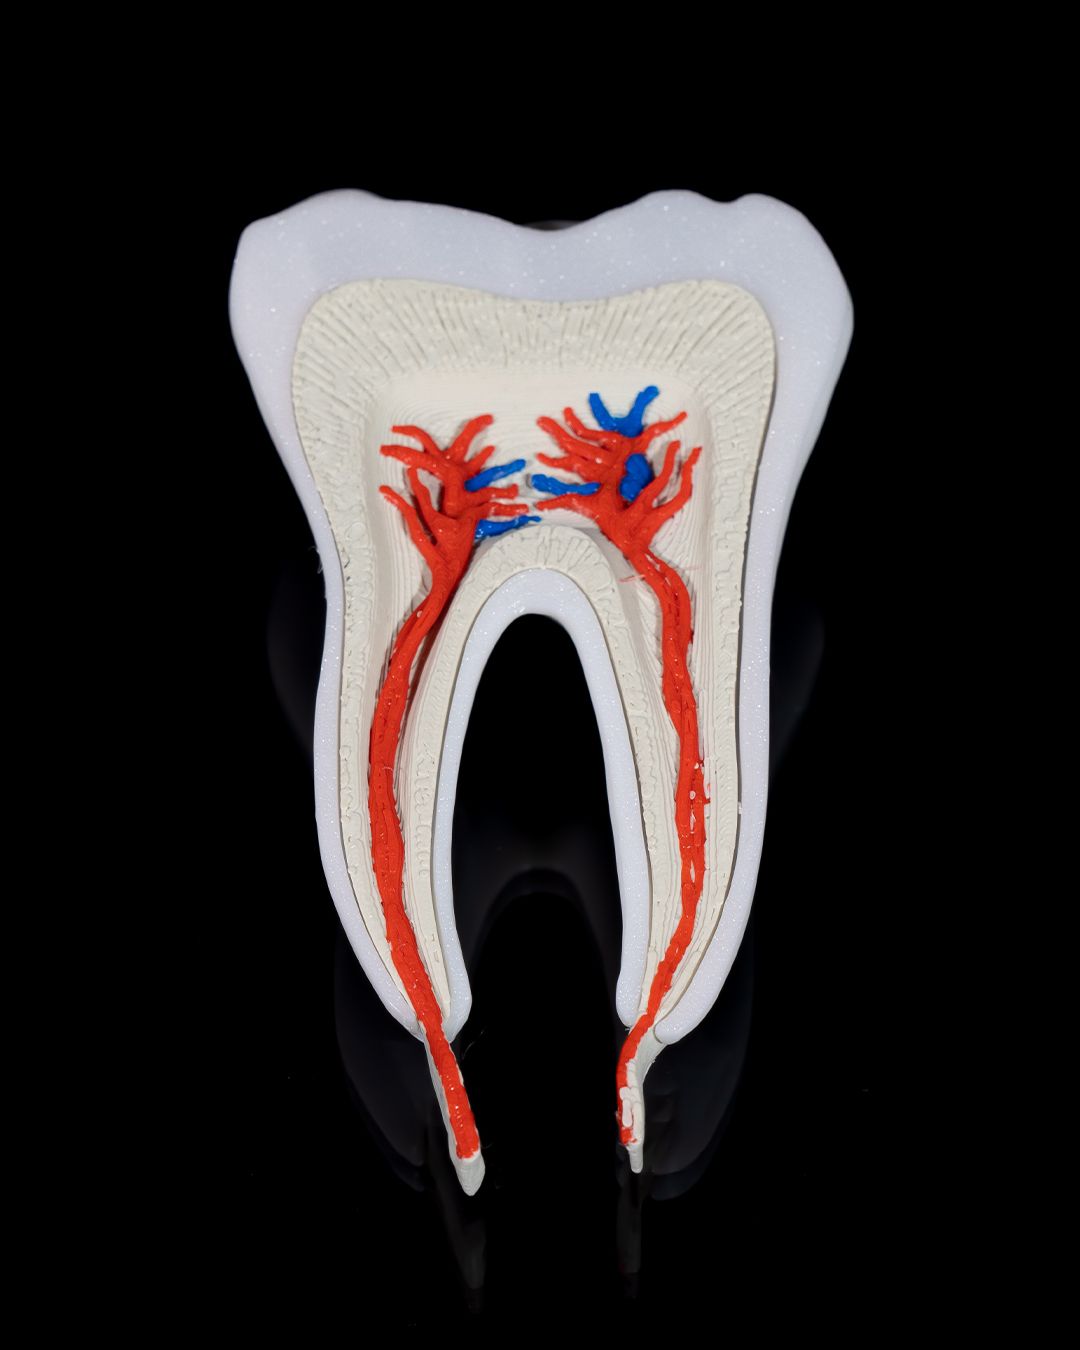

🦷 3D Printed Healthy Premolar Tooth – Precision You Can Smile About

Perfect for dental education, display, or interactive learning, this anatomically accurate premolar model showcases the structure and strength of a healthy adult tooth. It’s a striking blend of science and craftsmanship, ideal for classrooms, clinics, and curious minds.

- True-to-life size and shape for tactile exploration

- Clearly defined cusps, root formation, and enamel contours

- Excellent for explaining oral hygiene, dental anatomy, and procedures